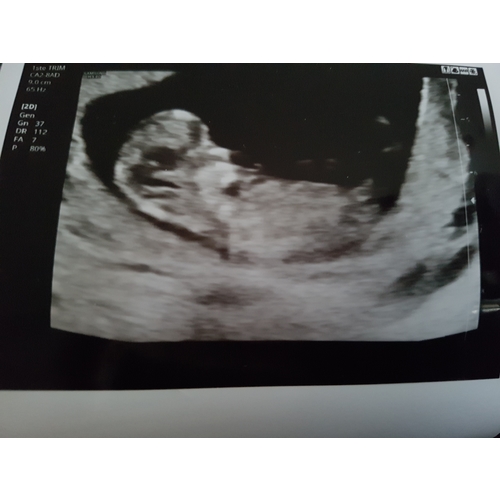

Moeilijk te zien.. maar hebben jullie een idee misschien? Nog 8 dagen.. dan ...

De nub is goed verborgen achter het beentje maar ik gok op boy 💙